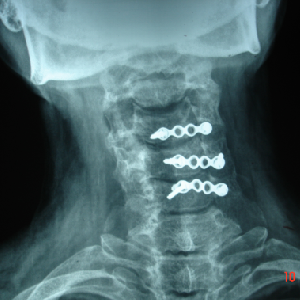

Generally cervical myelopathy with kyphotic cervical slpine is treated with anterior

decompression and fusion.

But this newer technique widely used in japan, allows posterior decompression with

preservations of movement at treated levels

Cervical Laminoplasty